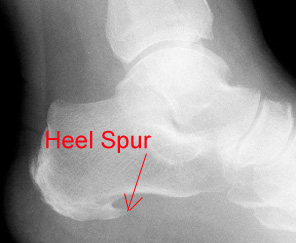

Heel spurs do not cause plantar fasciitis. It used to be thought that bony spurs found on the bone of the heel caused plantar fasciitis. However, there is no correlation between heel pain and the presence of a bony spur. Many people who never have had plantar fasciitis have heel spurs. The finding of a heel spur is an incidental finding but is often identified (incorrectly) as the source of the pain. So if you have a spur, fear not, with proper treatment you should be able to recover form plantar fasciitis and return to activity. - Ultrasound is useless for treating plantar fasciitis. Again, you might find this surprising because this treatment is used so commonly. A clincial study conducted by the medical department at the University of Sheffield and the London Foot Hospital found that ultrasound treatment was no more effective than a fake treatment.